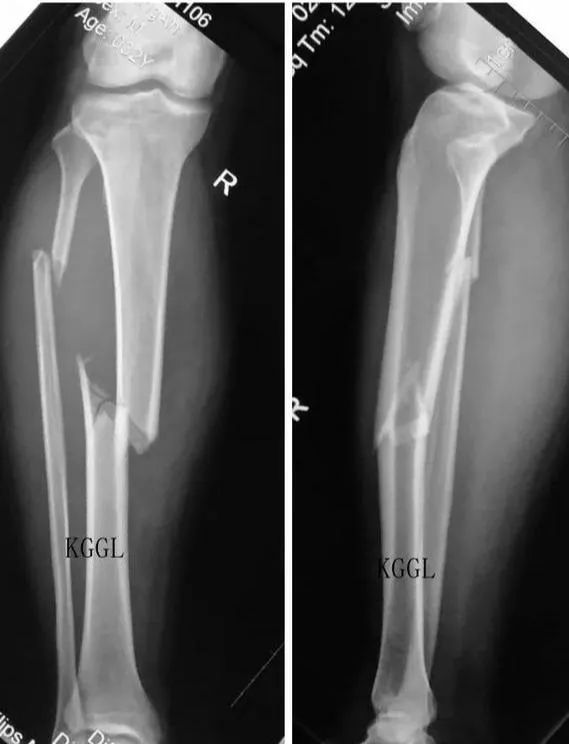

我打開慢的要死的電腦和卡的不行的工作站,調出他的片子。好傢伙,脛骨、腓骨都是粉碎性骨折,膝關節脛骨平台也受累了,這傷得不輕。明確病情之後,我把入院記錄和醫囑都搞定了。

類似於這樣